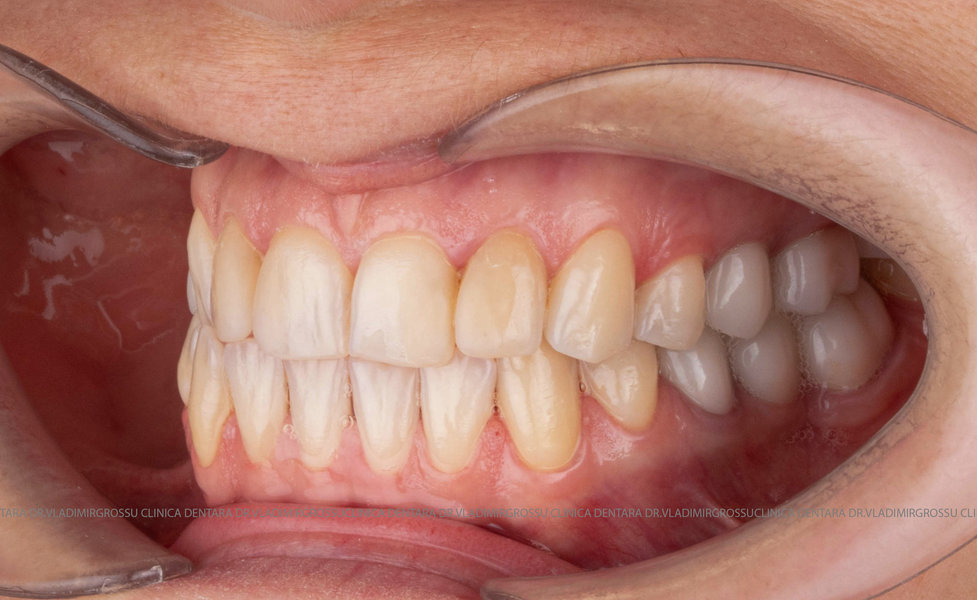

Cazuri clinice

Caz 1

Restaurări cu coroane din zirconiu vs fațete ceramice

Atât fațetele ceramice (Emax sau 360) cât și coroanele din zirconiu sunt soluții estetice eficiente. Fațetele sunt indicate pacienților cu o poziție dentară relativ uniformă și dinți vitali, deoarece implică șlefuirea minimală a smalțului (0,4–0,7 mm) și fixarea adezivă sub coferdam. În cazurile cu dinți tratați endodontic, coroane pigmentate, proteze pe implanturi sau când este necesară o creștere semnificativă a ocluziei, se preferă coroanele din zirconiu.